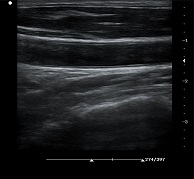

支持凸陣、線陣、腔內(nèi)、相控陣、小微凸等探頭

? ?● PHI脈沖反相組織諧波成像+頻率復(fù)合技術(shù)

? ? ? ?保證良好穿透力的同時(shí)獲得更加細(xì)膩的二維圖像